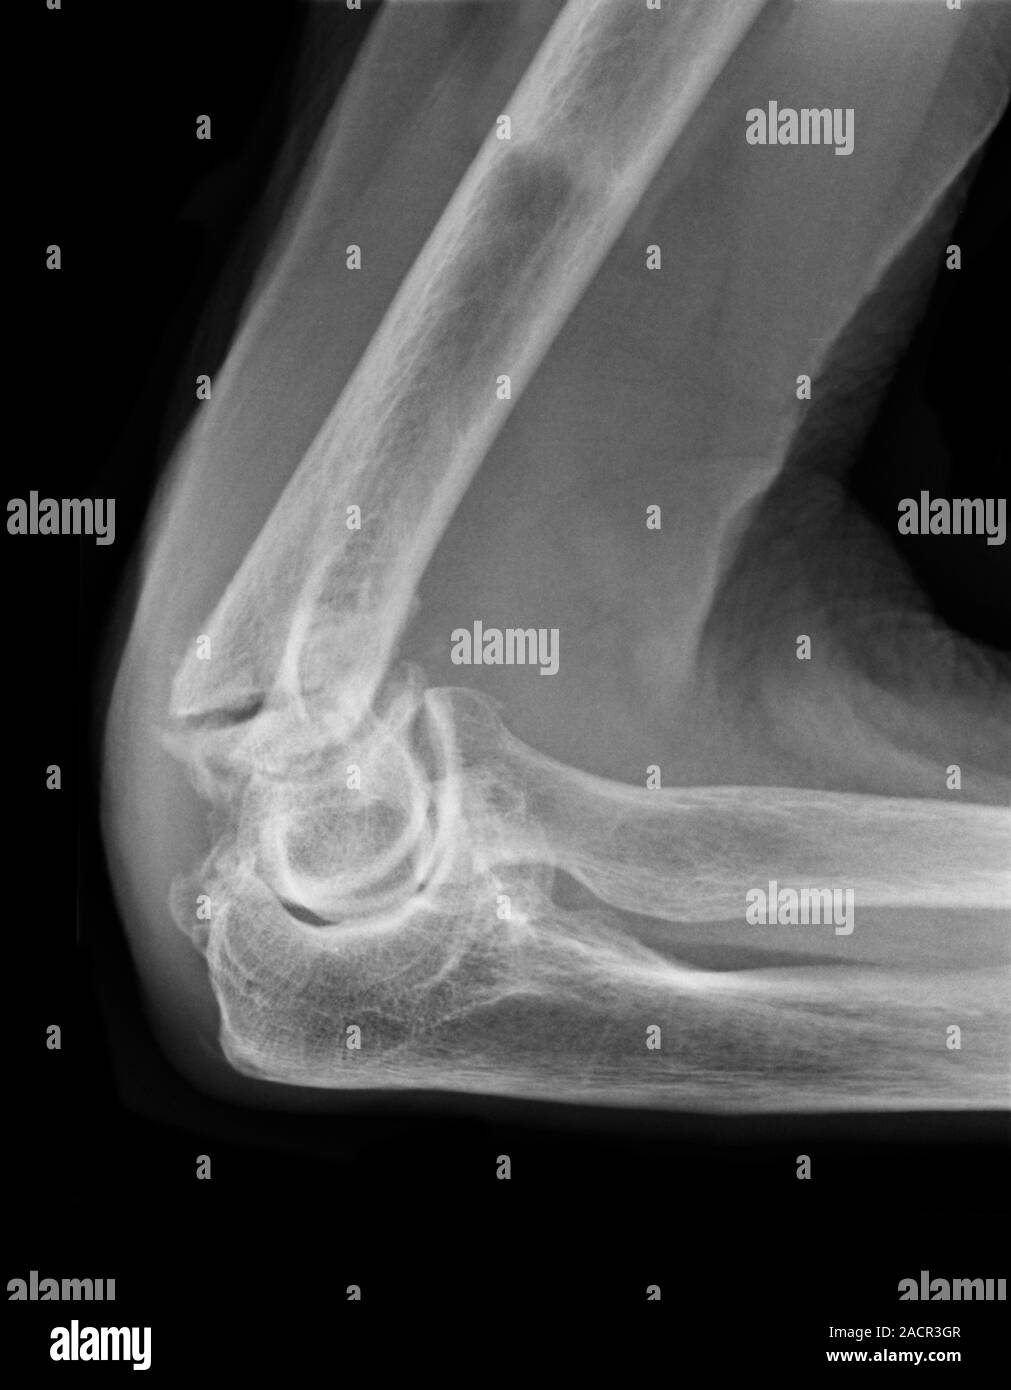

Fracture at neck of humerus ( arm bone ) ( film xray left shoulder and Arm Bone Humerus Fracture Fractures of the humerus usually result from falls or direct trauma. We’ll go over the locations of each type. mechanism of injury. a humerus fracture is a break of the humerus bone in the upper arm. A broken arm is a bone fracture (broken bone) in your arm. There are several types of humerus fractures, depending on the. Arm Bone Humerus Fracture.

Chest Xray (front view) showing a fracture to the arm bone (humerus Arm Bone Humerus Fracture There are several types of humerus fractures, depending on the location of the break. what is a broken arm? a humerus fracture is a break in the large bone of your upper arm. Symptoms may include pain, swelling, and bruising. a humerus fracture is the medical name for breaking the bone in your upper arm (your humerus).. Arm Bone Humerus Fracture.

Human Shoulder with Xray Show Fracture at Neck of Humerus Arm Bone Arm Bone Humerus Fracture We’ll go over the locations of each type. a humerus fracture is the medical name for breaking the bone in your upper arm (your humerus). mechanism of injury. A broken arm is a bone fracture (broken bone) in your arm. a humerus fracture is a break of the humerus bone in the upper arm. Fractures of the. Arm Bone Humerus Fracture.